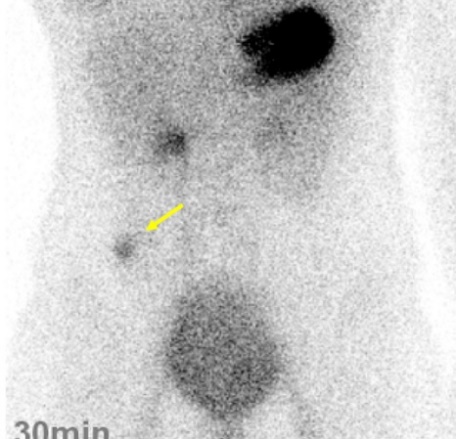

Xạ hình với Technetium Tc 99m pertechnetate:

Chất này được biết được tích tụ ở niêm mạc dạ dày. Nó được dùng để phát hiện túi thừa Meckel có chứa biểu mô niêm mạc dạ dày lạc chỗ.

Hình 5. Hình ảnh xạ hình ổ bụng với Tc 99m pertechnetate

* Nguồn: theo Irie T. (2016) [6]

Người ta thấy rằng những đảo niêm mạc như vậy với đường kính > 1 cm có thể phát hiện bằng phương pháp này với độ chính xác 90% ở trẻ em và dưới 50% ở người lớn[5]. Sau khi tiêm tĩnh mạch 30 đến 50 μCi/kg chất có hoạt tính phóng xạ trên rồi chụp phim thẳng 10 phút 1 lần ít nhât trong vòng 1 giờ để phát hiện các vùng tích tụ thuốc bất thường ngoài dạ dày. Túi thừa meckel được phát hiện nhờ một vùng hấp thu khu trú tồn tại dai dẵng ở hố chậu phải hay giữa ổ bụng (Hình 5).60% các trường hợp túi thừa Meckel có triệu chứng có niêm mạc dạ dày lạc chỗ và 98% các bệnh nhân này có biểu hiện chảy máu đường tiêu hóa. Vì vậy đây là phương pháp rất tốt để chẩn đoán. Tuy nhiên Bệnh viện chúng tôi chưa có phương tiện này.